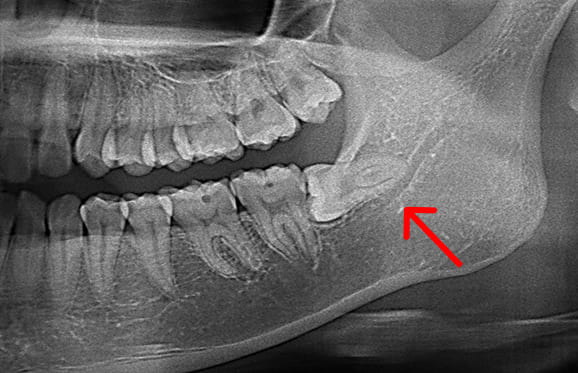

● C4を超え歯根までの虫歯を抜歯、親知らずを利用して歯並び全体を整えた症例

藤沢デンタルオフィスの虫歯や破折で抜歯後の部分矯正